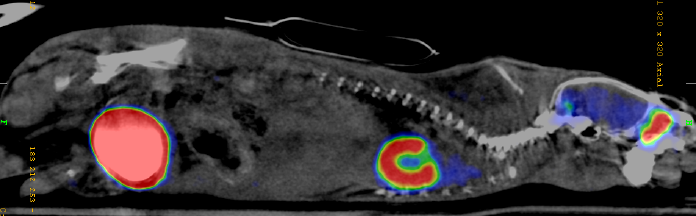

Legene bruker en PET/CT-skanner ved diagnostisering og behandling av kreftpasienter. PET/CT-bilder kan nemlig se hvor i kroppen kreften er, siden kreftceller vil lyse opp på bildet. For kreftpasienter er det svært viktig å vite hvor i kroppen kreftcellene sitter, fordi behandlingen av sykdommen ofte er tett knyttet til nettopp dette.

PET/CT: En sammensetning av PET og CT, hvor bildene sys sammen for å vise anatomi og sporstoffer samtidig.

PET-skanneren kan oppdage slike lysglimt fra sammentreff mellom et positron og et elektron. Når PET-skannerne har målt mange slike lysglimt kan vi si hvor positronene var til å begynne med. Da får vi et bilde av hvor sporstoffet befant seg i kroppen – eller hvor kroppen har et høyt forbruk av sukker.